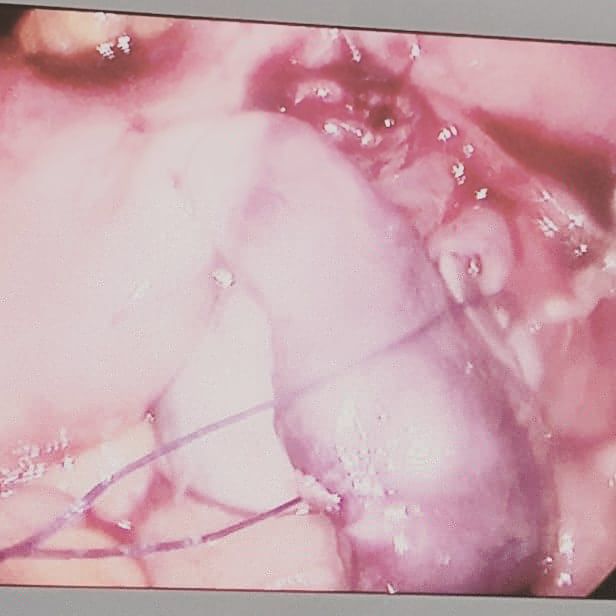

Mi experiencia abarca un espectro diverso, desde apendicitis hasta afecciones de la vesícula biliar, el colon y el recto. Como especialista en Laparoscopia, estoy dedicado a utilizar técnicas avanzadas y soluciones personalizadas para abordar las necesidades únicas de cada paciente.

• Cirugía laparoscópica

• Quistectomía de ovario por laparoscopia